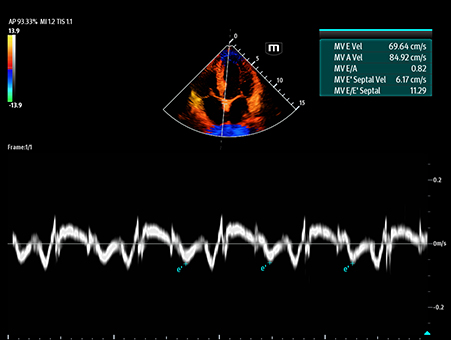

Mindray's Emergency Ultrasound Solutions address clinical challenges through a systemic approach. Those solutions cover the entire emergency care process from pre-hospital rescue and ambulance transport to ER treatment and in-hospital transfer. The versatility of Mindray Ultrasound shaping from Tablet system, Laptop-based system to Handheld Ultrasound system brings up the power of Ultrasound at the point of care. Clinical oriented smart features and protocols assist decisions with confidence.